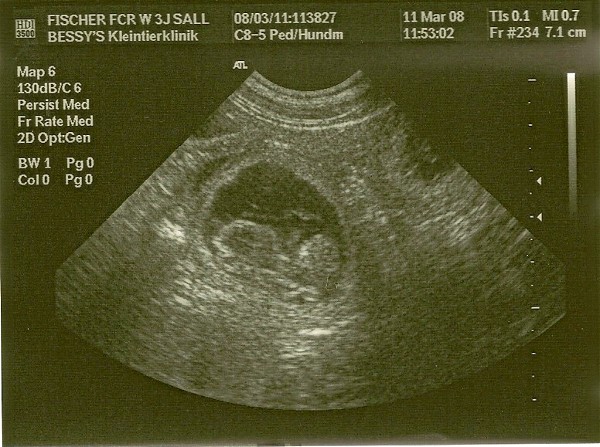

11. März 2008 Ultraschall

Am 11. März kommt dann endlich die Bestätigung - der Ultraschall zeigt, dass Sally definitiv trächtig ist.